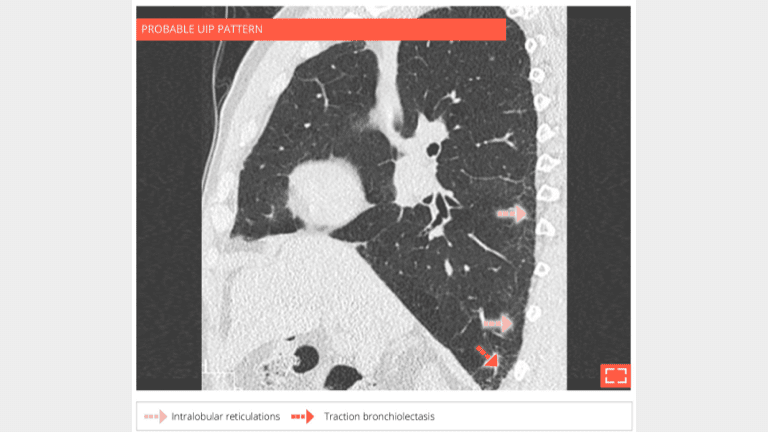

• Isolated and subtle subpleural intralobular reticulations and traction bronchiectasis of the 2 lower lobes.

• No ground-glass opacity or honeycombing.